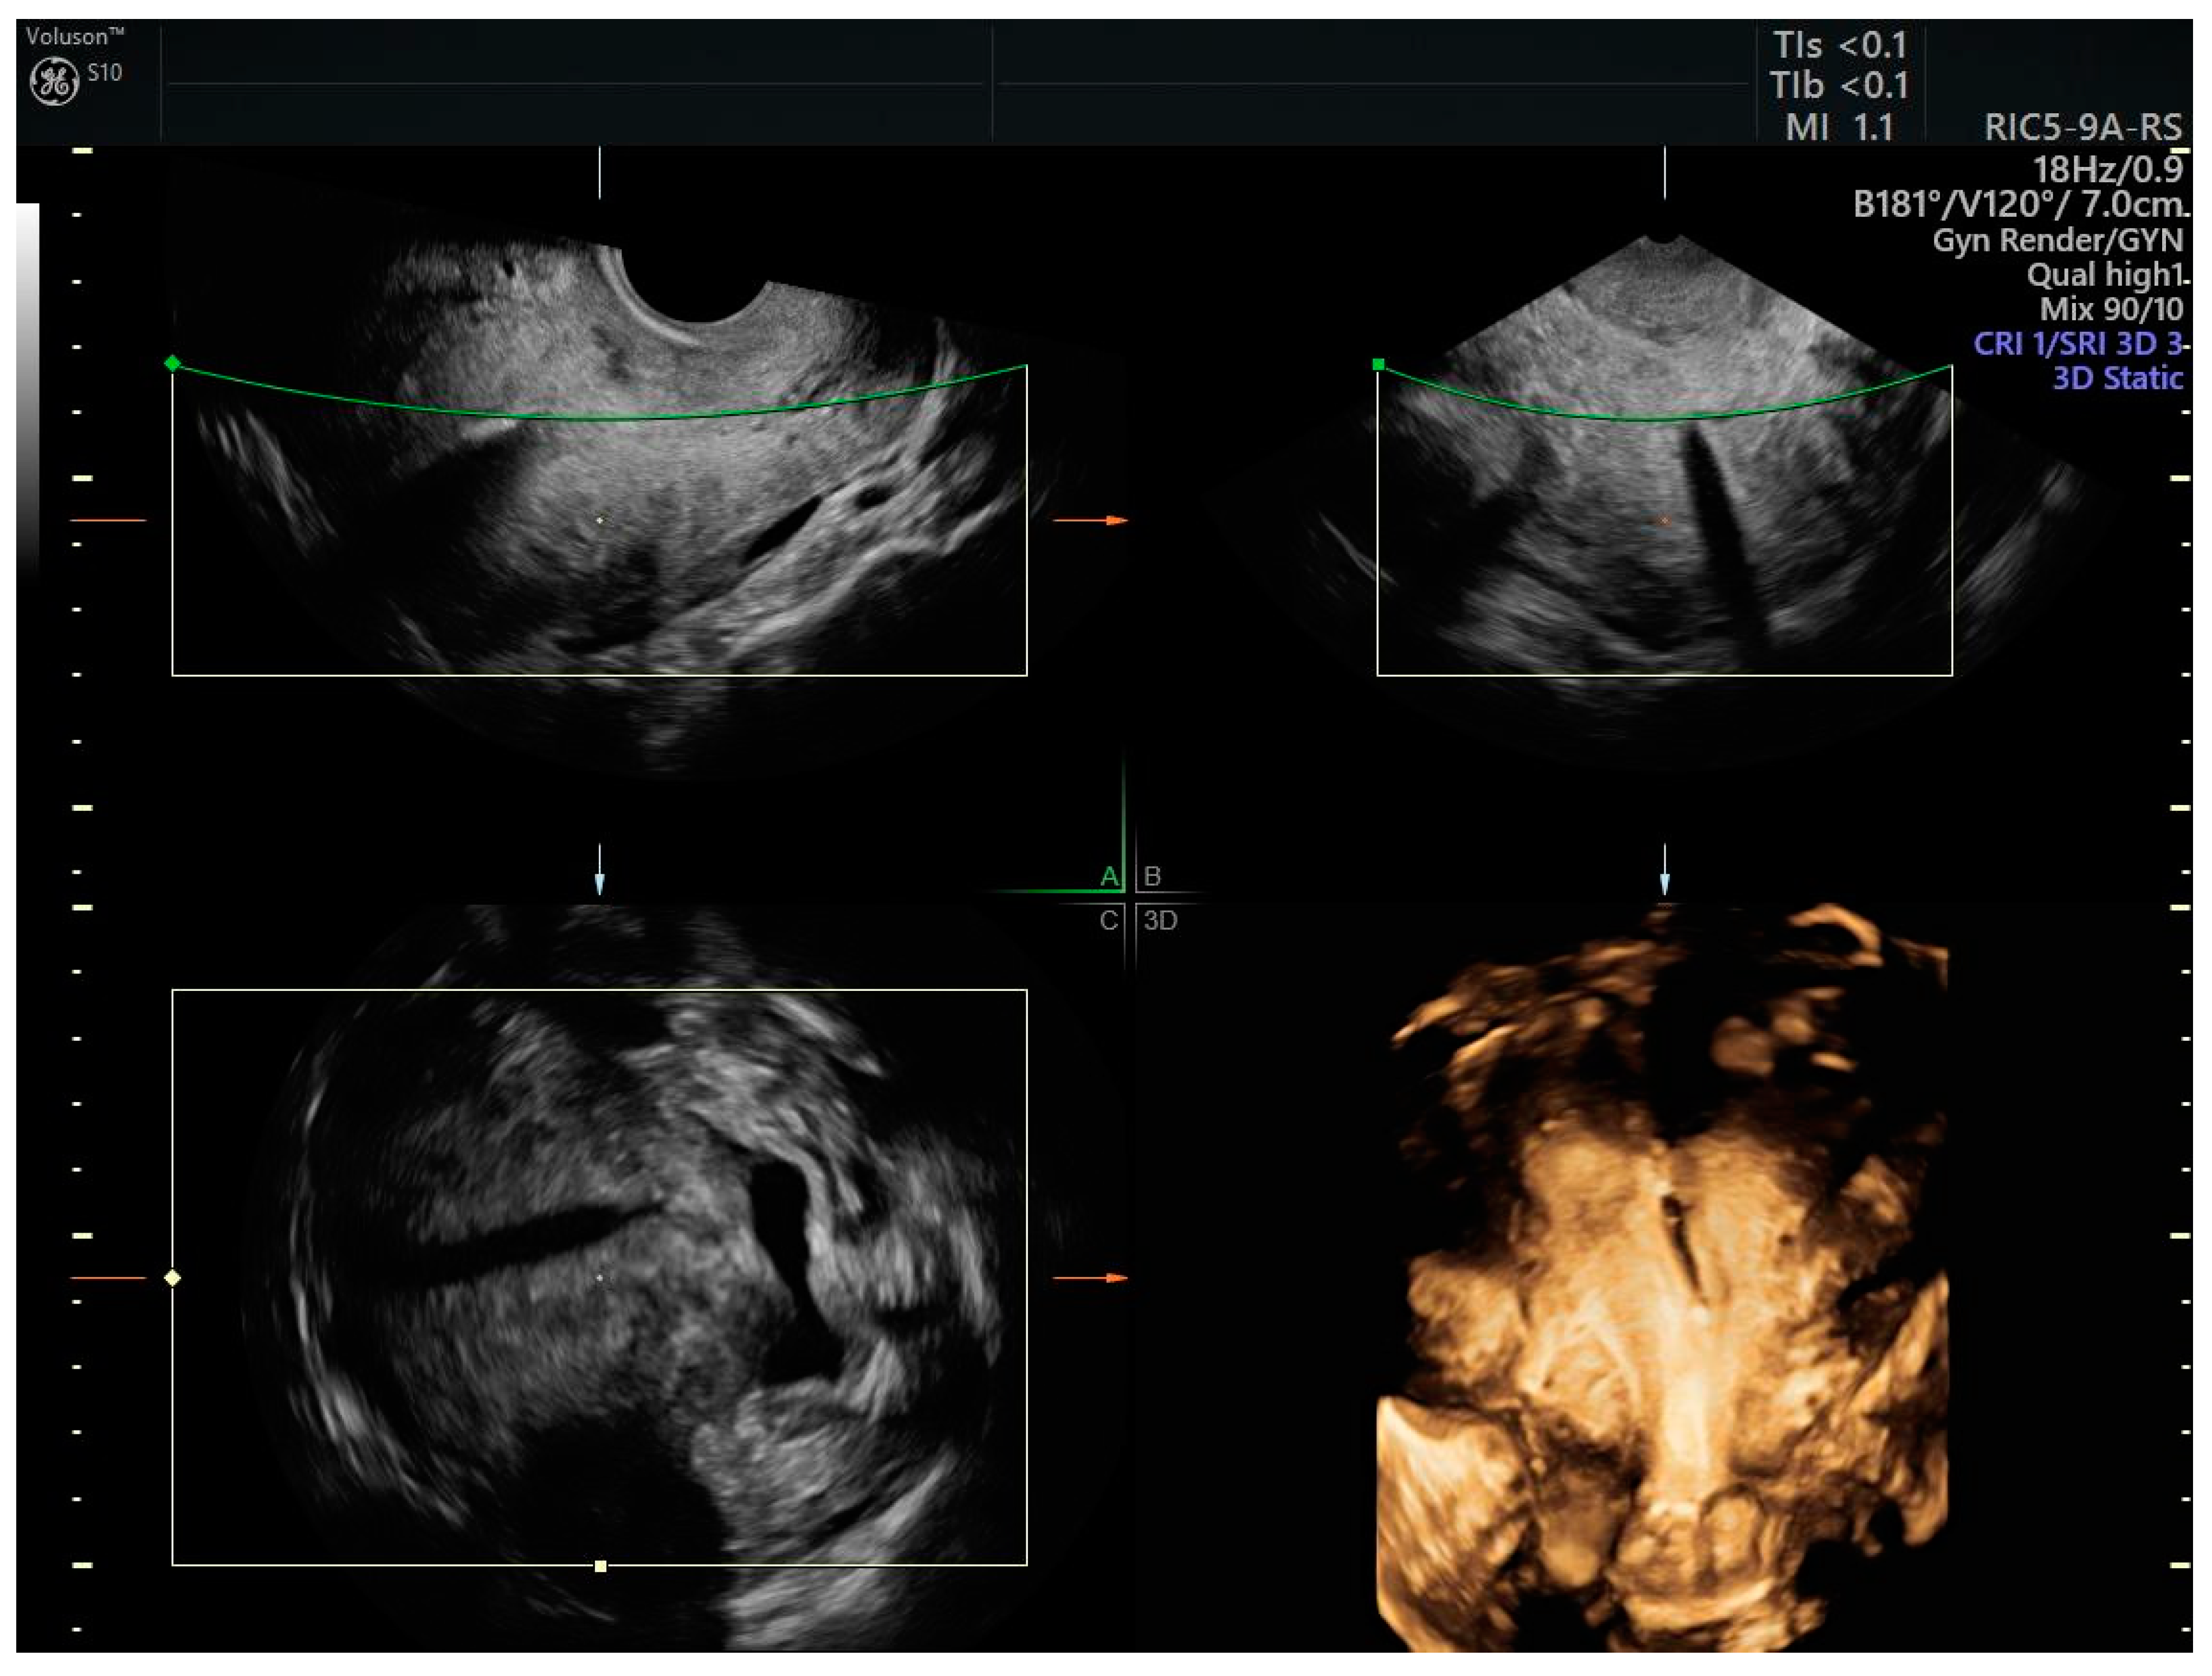

The LNG-IUD (Figure 2) in 57 patients (21 endometrial cancer, 36 complex atypical hyperplasia) showed a complete response in 91% of women with hyperplasia with atypia and 54% of women with endometrial cancer within 12 months of treatment [23].

Figure 2.

3D scan of the uterus of a patient with endometrial cancer treated with LNG-IUD. The correct positioning of the intrauterine device is monitored by ultrasound, which also allows the identification of any changes in the endometrial pattern during treatment.